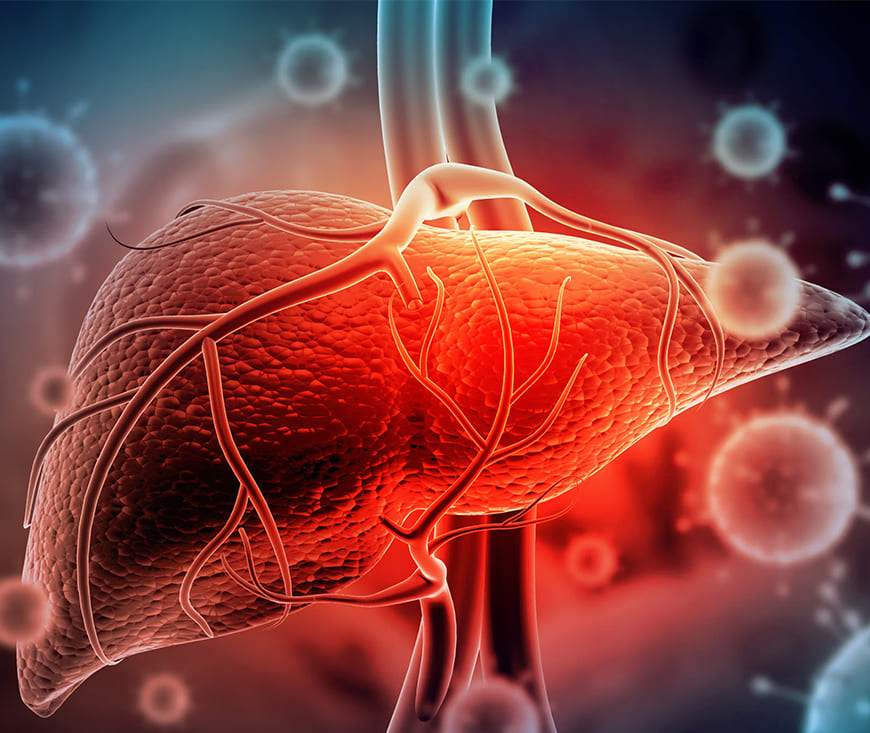

Hepatitis treatment focuses on reducing inflammation and preventing liver damage. Antiviral medications, lifestyle changes, and proper medical care help manage the condition. For chronic hepatitis, medications like interferon or direct-acting antivirals may be used. Early detection and regular monitoring are essential for effective management and improving quality of life.

Liver cirrhosis treatment aims to manage symptoms, slow progression, and prevent further liver damage. Medications, lifestyle changes, and a healthy diet are crucial. In advanced cases, a liver transplant may be necessary. Early diagnosis, regular monitoring, and medical care can improve outcomes. Consult a healthcare provider for personalized treatment and care options.

Fatty liver disease treatment focuses on lifestyle changes and managing underlying conditions. A balanced diet, regular exercise, and weight loss are essential in reducing liver fat. Medications may be prescribed for related conditions like diabetes or high cholesterol. Early diagnosis, along with regular monitoring, can prevent complications. Always consult a healthcare provider for personalized treatment.

Alcoholic liver disease treatment involves stopping alcohol consumption to prevent

further liver damage. Medical interventions may include medications to manage symptoms,

treat complications, and support liver function. A balanced diet, weight management, and

regular monitoring are crucial. In severe cases, a liver transplant may be necessary.

Hepatitis is an inflammation of the liver, commonly caused by viral infections (A, B, C) or excessive alcohol use. Treatment depends on the type and severity of the condition. Antiviral medications, lifestyle changes, and regular monitoring help manage chronic hepatitis. In severe cases, a liver transplant may be required. Early detection and medical guidance are essential for effective treatment